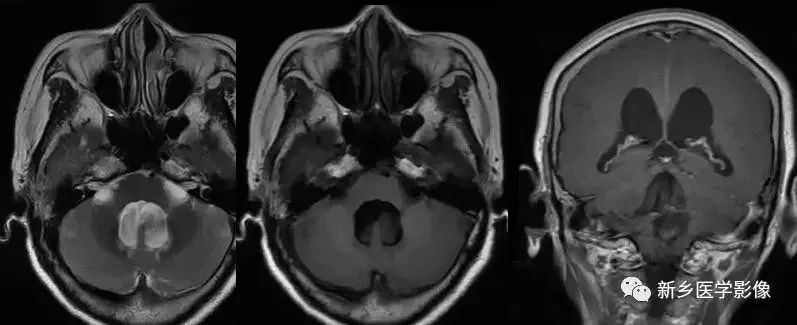

❹ Dandy-Walker’s综合症

又称第四脑室中侧孔先天性闭锁。在胚胎早期期,第四脑室正中孔及侧孔闭寒,导致四脑室呈囊性扩张,并伴有小脑蚓部及半球发育不良,扩张之四脑室向后发展,并与枕大池相连,使后颅窝扩大,小脑幕抬高。本病出现脑积水通常见于婴儿期,或者出生后即存在,但到成人期才发病。

❺ 四脑室内囊肿

四脑室囊肿可引起整个脑室系统梗阻扩大。

❻ 孤立性第四脑室

当导水管和第四脑室出口严重狭窄或完全阻塞时,四脑室则被孤立起来,这种情况称为孤立性第四脑室。